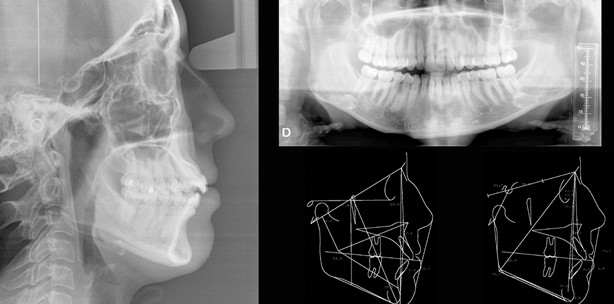

Die Kraniomandibuläre Dysfunktion ist gekennzeichnet durch einen myofaszialen Schmerz, der Patienten oft über längere Zeiträume belastet. Ein Protein spielt scheinbar eine große Rolle bei einer Kraniomandibulären Dysfunktion (CMD). Das Protein TRPV4 hat großen Einfluss darauf, wie stark Schmerzen im Kiefer empfunden werden. Wissenschaftler der Duke University arbeiten nun daran, dieses Eiweiß medikamentös auszuschalten und so dem Patienten die Schmerzen zu nehmen.

Das Tunnelprotein TRPV4 erlaubt es Kalziumionen schnell in Biomembranen vorzudringen. So dringt es auch in die Neuronenrezeptoren im Ganglion Gasseri vor. Dieses ist für alle Reizempfindungen im Kopf-Hals-Bereich verantwortlich. Im Versuch verglichen die Forscher normale Mäuse und Knockout-Mäuse, bei denen TRPV4 deaktiviert wurde. Beiden Mäusegruppen wurde im Kieferknochen eine Entzündung induziert. Beim Vergleich der Bissstärke zeigte sich, dass die Knockout-Mäuse deutlich stärker zubissen. Auch wenn bei den Mäusen ein entsprechender Gewebeschaden im Kieferbereich vorlag, schienen sie aber nicht den Schmerz bei der Beißbewegung zu empfinden, den die „normalen“ Mäuse empfanden.

Eine gezielte Medikamentierung gegen das Protein TRPV4 könnte daher eine Abhilfe für CMD-Patienten schaffen, um die Schmerzen rasch auszuschalten, während eine langfristige physische Therapiemaßnahme vorgenommen werden kann.